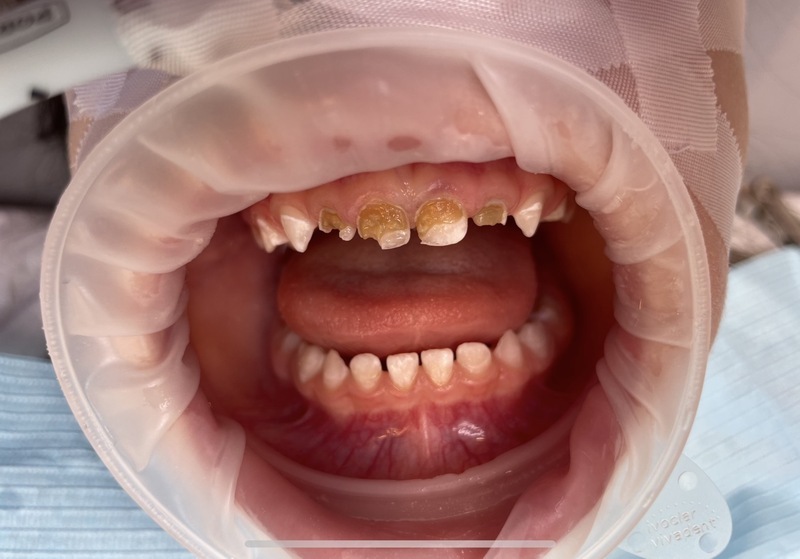

Situace se v některých oblastech zlepšuje, ale stále existuje velká skupina lidí, kteří péči o zuby zanedbávají. „Kazivost zubů je v Česku stále poměrně vysoká a řešení následků komplikované a drahé,“ dodává. Trend „rozevírajících se nůžek“ mezi těmi, kdo prevenci dodržují, a těmi, kdo zanedbávají, je patrný.

Jednoduché pravidlo „Čistý zub se nezkazí“ shrnuje princip prevence: kaz vzniká, když na zubech zůstává bakteriální plak. Pravidelné a důkladné čištění chrání zuby. Důležitá je i role rodičů: děti si zuby správně vyčistí samy až kolem deseti let, do té doby je třeba je učit a kontrolovat.